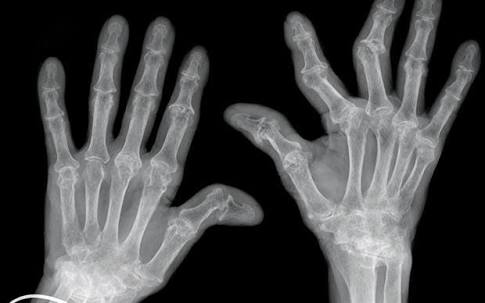

当然当很多患者已经到了晚期,关节已经出现了明显的变形,从相关的查体以及x光片子,也可以明确患者是否存在类风湿性的关节炎。从下图您仔细看就会看出正常的手与类风湿性关节炎手部的骨骼改变。

另外类风湿这种疾病也会导致患者出现比较严重的骨质疏松,建议类风湿患者一定要做双能x线检查,明确自己是否存在骨质疏松,或者说骨质疏松到了什么样的程度,根据结果进行系统的抗骨质疏松治疗。